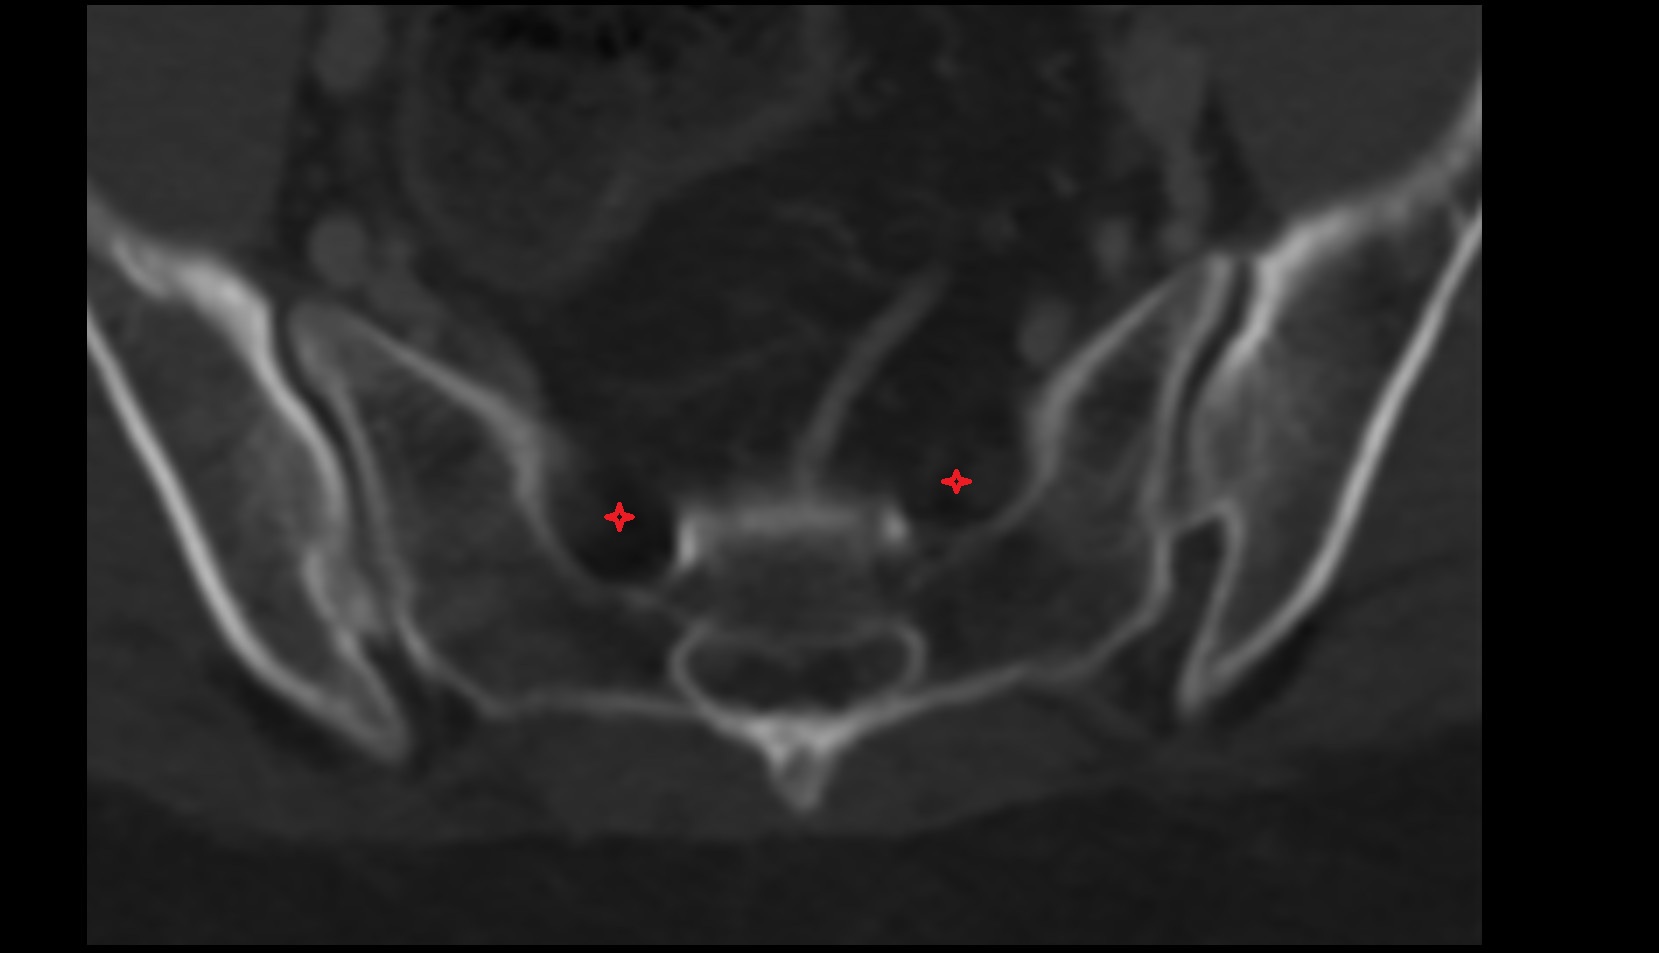

- Anterior sacral foramina

- Spinal nerve S1

- Spinal nerve S2

- Spinal nerve S3

- Spinal nerve S4